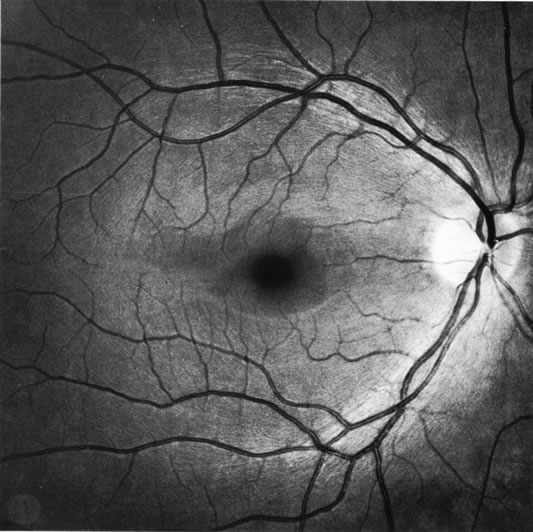

The approximately 1 to 1.5 million axons that form the optic nerve arise from the retinal ganglion cells and course toward the optic disc in a well-known pattern (Fig. 1). From the nasal retina the fibers take a straight course toward the disc. Axons originating temporal to the fovea arc around the macula to enter the upper and lower poles of the optic nerve head. The macula fibers pass directly to the temporal quadrant of the disc in the papillomacular bundle.

Fig. 1. Fundus photograph shows the normal pattern of the retinal nerve fiber layer. (Courtesy of P. Juhani Airaksinen, MD).